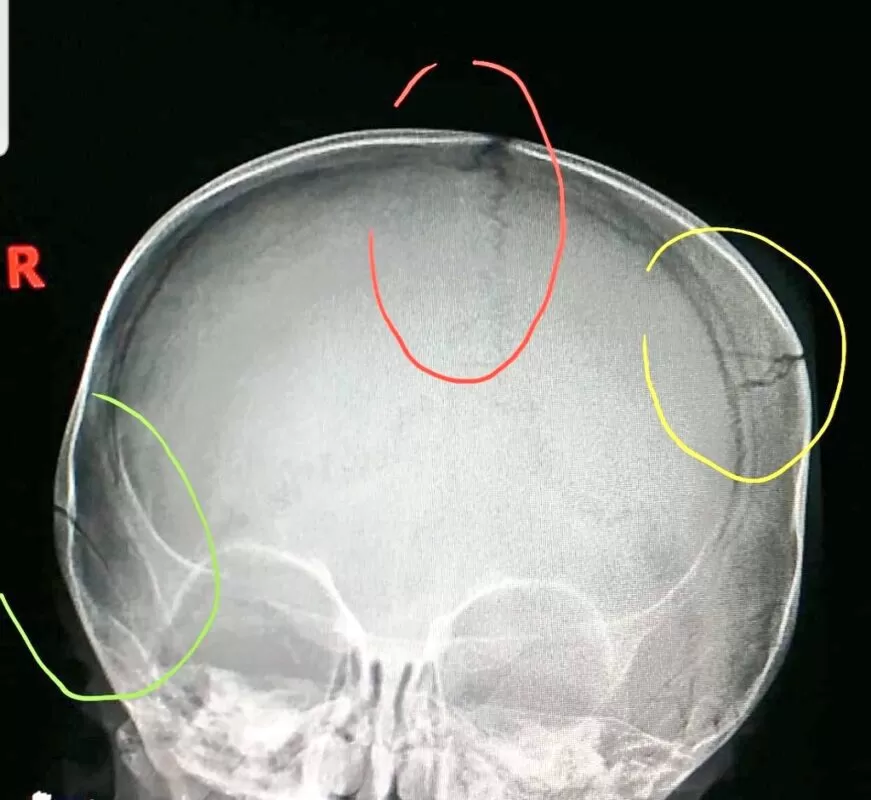

أنواع كسور عظام الجمجمة

تختلف أنواع كسور عظام الجمجمة بناءً على قوة الضربة التي تعرضت لها الرأس ومكانها وشكل الجسم الذي يصطدم بالرأس.

الكسر المغلق (Closed fracture)

يعد الكسر المغلق أو الكسر البسيط أكثر أنواع كسور الجمجمة شيوعاً، يحدث الكسر المغلق في خطوط محددة بالجمجمة ولا توجد انخفاضات في عظم الجمجمة أو قطع في الجلد.

كسر الجمجمة المنخسف (Depressed fracture)

يكون جزء من الجمجمة منخفض أو منخسف يمتد إلى تجويف المخ بسبب التعرض إلى صدمة.